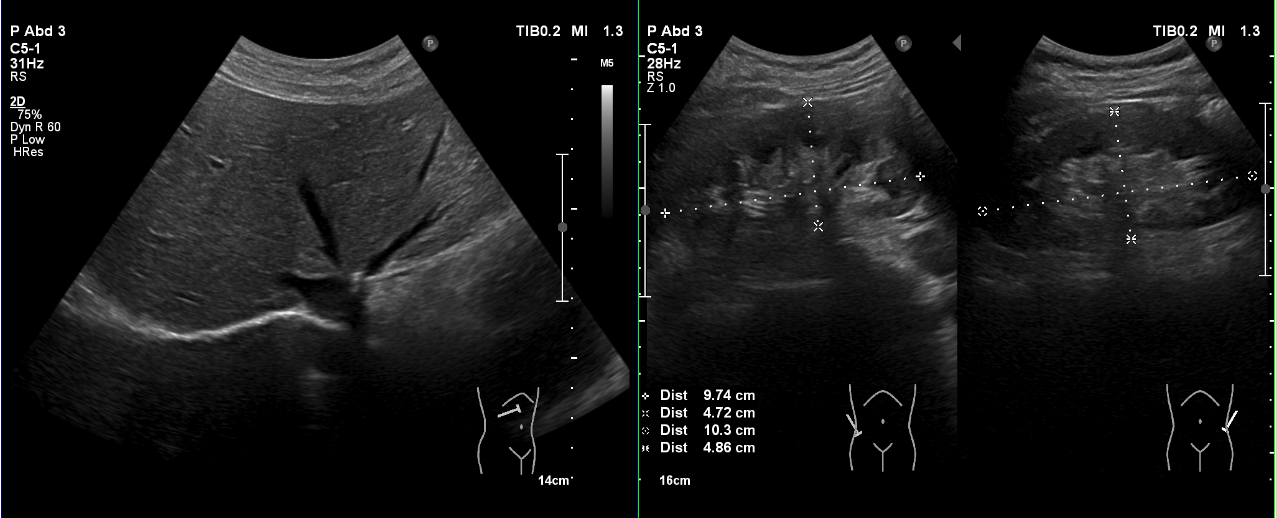

| 超音波検査 |

超音波装置を用いて、心臓や腹部(肝臓・胆のう・膵臓・腎臓・脾臓・膀胱など)、血管の状態を観察します。腹部エコー検査は空腹で行います。